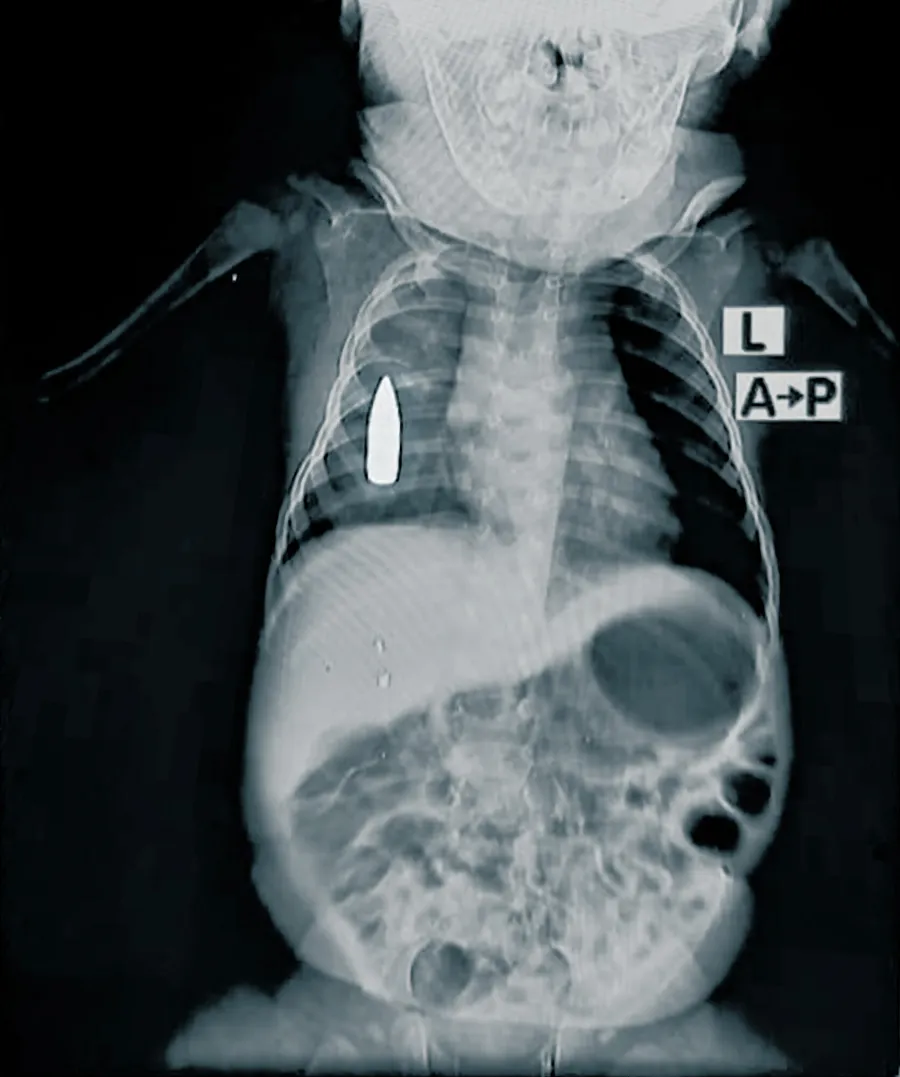

November 2024: Ein 18 Monate altes Kleinkind wurde von einer Kugel in die Brust getroffen, während es in Khartum ein Nickerchen gemacht hat. Es wurde in die Notaufnahme des Bashair Lehrkrankenhauses gebracht. Den Chirurg:innen gelang es, sein Leben zu retten, aber die Kugel blieb im Körper. Die Ärzt:innen sind bemüht, die Kugel zu entfernen, es gibt aber im Moment keine funktionsfähige Spezialklinik und die Zufahrtswege zu anderen Krankenhäusern sind blockiert.